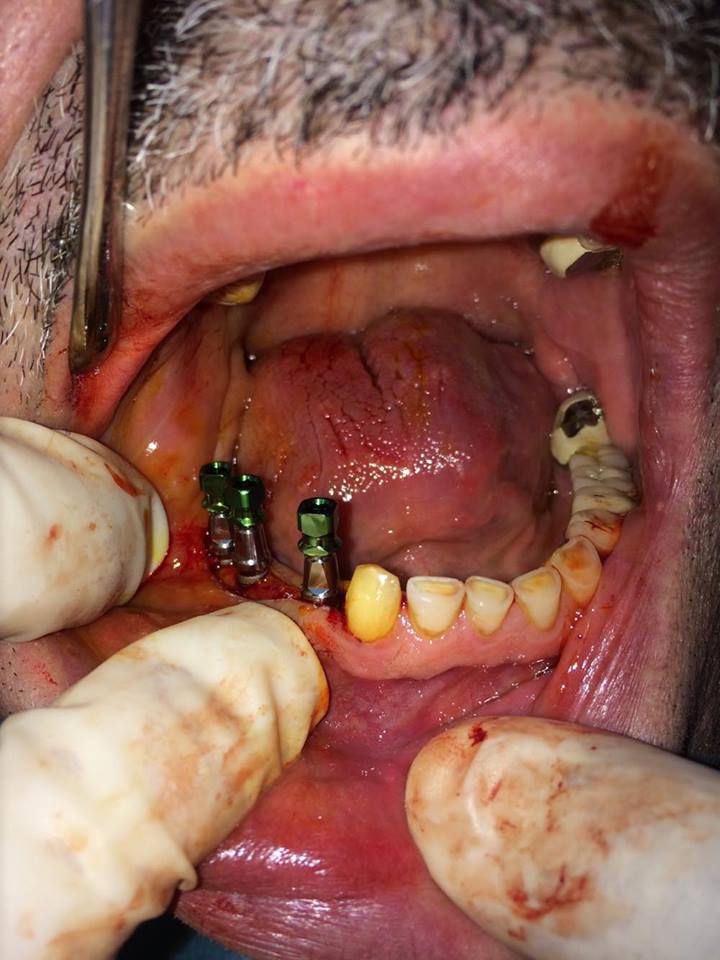

İMPLANT TEDAVİSİ

implant tedavisi